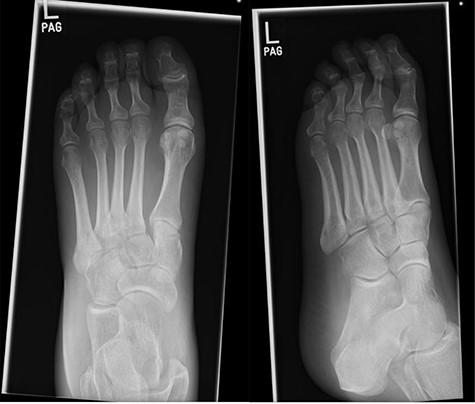

At this presentation, plain film X-ray revealed complete fracture dislocations of the second to fifth tarsometatarsal joints, involving the lateral, middle and medial cuneiform bones of the left mid-foot (Lisfranc fracture dislocations; Fig. 3). This was correlated with bone CT (computed tomography) and MR (magnetic resonance) imaging, with interval changes noted to be of rapid onset (Fig. 4).

Foot X-rays taken at acute presentation (AP and lateral views), demonstrating rapid interval progression and destruction to mid-foot.